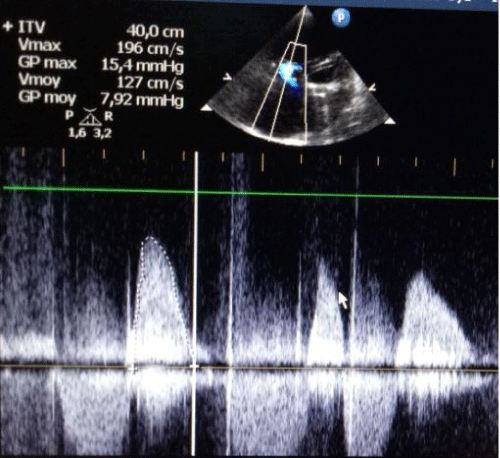

According to hemodynamique measurements, once inflation was complete, the mean pressure gradient was reduced to 5 mmHg. The right atrial pressure dropped from 46 mmHg to 23mmHg. Post procedure transthoracic echo cardiography showed that mean gradient was reduced from 12 mmHg to 6 mmHg (Figure 3). The tricuspid régurgitation was inchanged. The patient tolerated the procedure well.